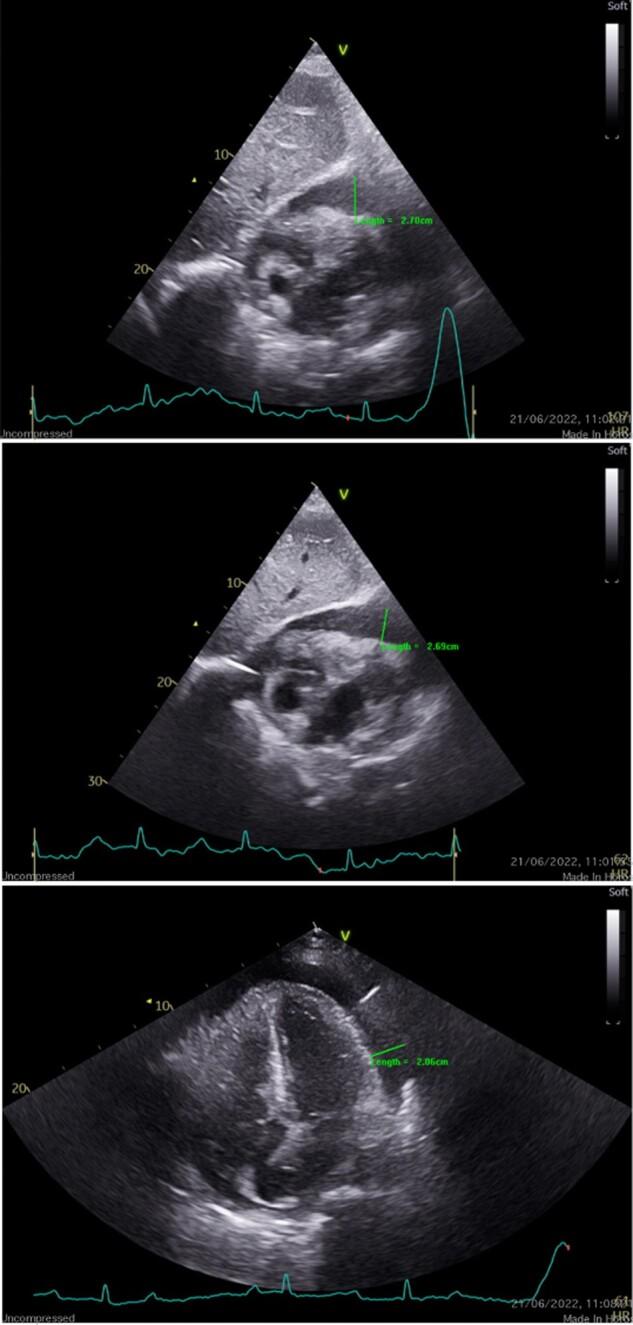

An 80-year-old Caucasian female presented with complete heart block and symptomatic cardiac tamponade. A pericardiocentesis was performed and a dual-chamber permanent pacemaker was implanted for the management of her complete heart block. Subsequently, a right atrial mass was discovered on imaging and the patient underwent endomyocardial biopsy of the mass. Histological analysis of the sample confirmed a primary cardiac lymphoma. The patient opted to forgo treatment with chemotherapy and died from her disease 1 month later.

一名80岁的白人女性出现完全性心脏传导阻滞和有症状的心包填塞。进行了心包穿刺,并植入了双腔永久起搏器以治疗其完全性心脏传导阻滞。随后,影像学检查发现右心房有肿块,患者接受了该肿块的心内膜活检。样本的组织学分析证实为原发性心脏淋巴瘤。患者选择放弃化疗,1个月后死于该疾病。